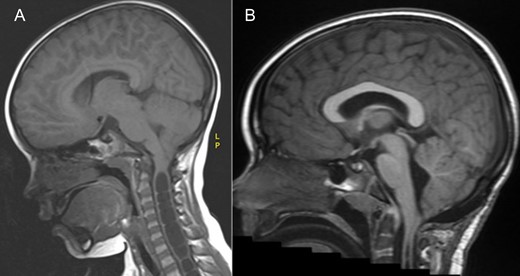

An MRI demonstrated a chiari one malformation (Fig. 1) with holocord syrinx (Fig. 2). No space occupying lesion was seen in the spine and the cord was not tethered. Neurophysiological investigations were carried out (Fig. 3), the child found the nerve conduction studies (NCS) and electromyography (EMG) difficult to tolerate however the findings were in keeping with pre-ganglionic pathology. There was evidence from the motor NCS and EMG of neurogenic abnormalities, including active denervation and re-innervation at the L4/5 level. These findings could have been at the level of the root or anterior horn. However, these findings were not considered typical for a peroneal neuropathy as the peroneal sensory potential was within normal limits.

MRI brain demonstrating the chiari 1 malformation. Pre-op sagittal T1 showing cerebellar tonsillar descent of 9 mm below the foramen magnum (A) and at 3 years post op showing adequate hind brain decompression (B).

At 1 year follow-up, his foot drop had gradually improved. He was able to walk on his tip toes and heels. By 2 years follow-up, his foot drop had completely resolved and ankle dorsiflexion was 5/5 on the right. An MRI at three years post op demonstrated a good foramen magnum decompression (Fig. 1) and significant improvements in the syrinx (Fig. 2), however not complete resolution.